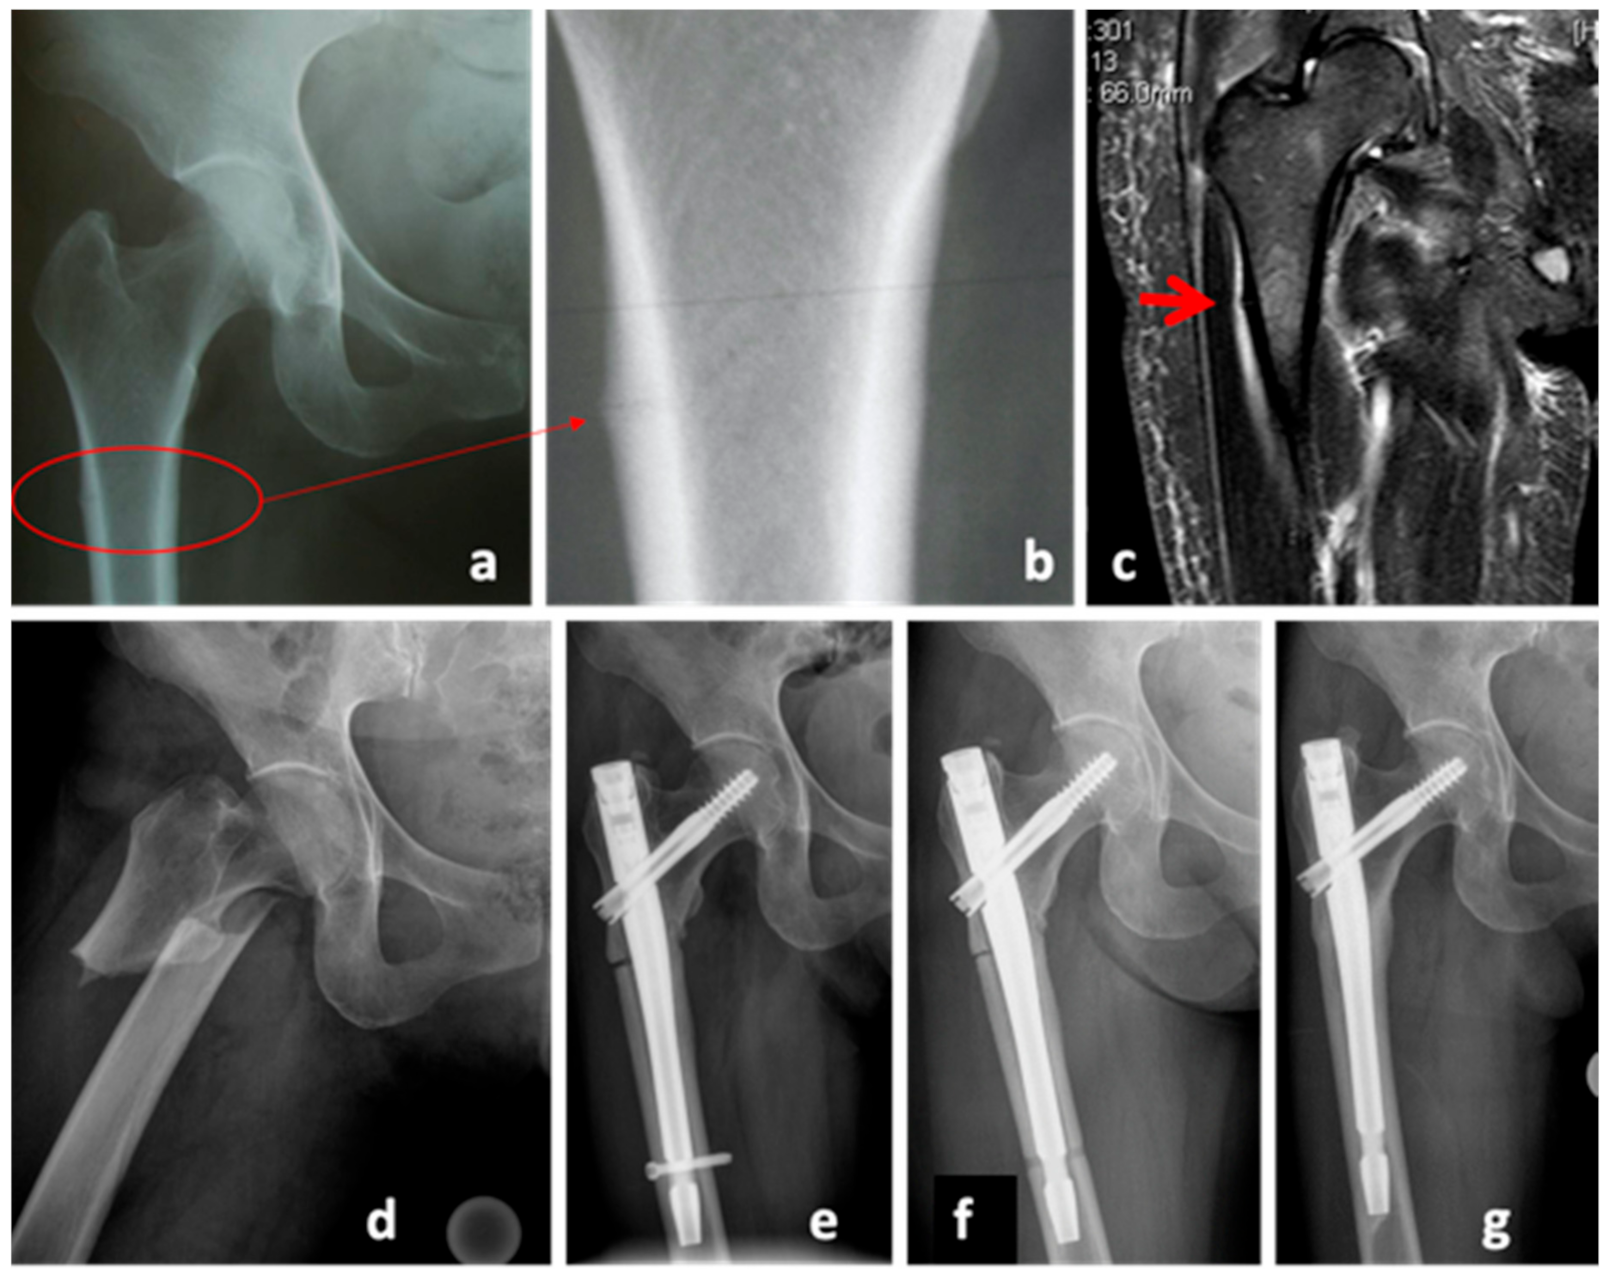

2. Case Series